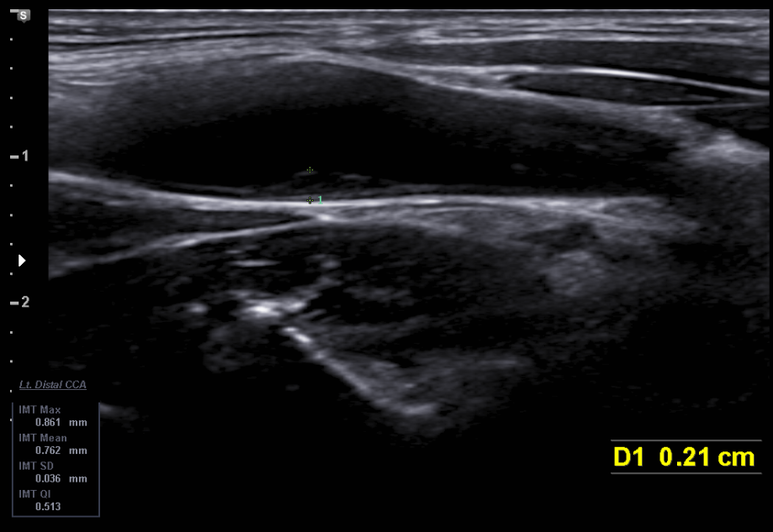

경동맥 내막 비후